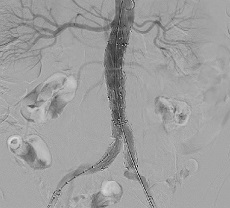

下肢動脈造影

下肢を栄養する動脈の形状、血流を評価する目的で行われます。

カテーテルを通して造影剤を注入します。撮影した血管の状態により、治療方針が決定します。